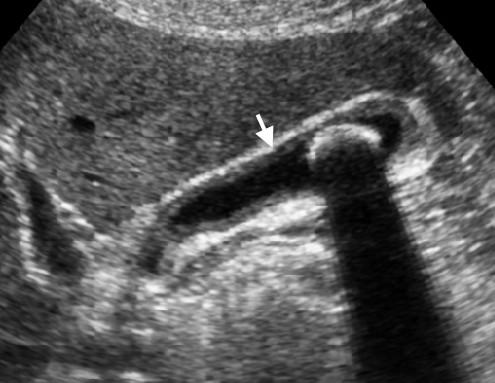

TRÁI: Siêu âm túi mật bình thường sau nhịn ăn qua đêm cho thấy thành túi mật là một đường tăng âm mỏng như bút chì (mũi tên). PHẢI: Siêu âm ở trạng thái sau ăn cho thấy hình ảnh dày thành túi mật giả.

Thành túi mật bình thường trên siêu âm có hình ảnh là một đường tăng âm mỏng như bút chì.

Độ dày thành túi mật phụ thuộc vào mức độ căng giãn của túi mật và hiện tượng dày thành giả có thể xảy ra ở trạng thái sau ăn.